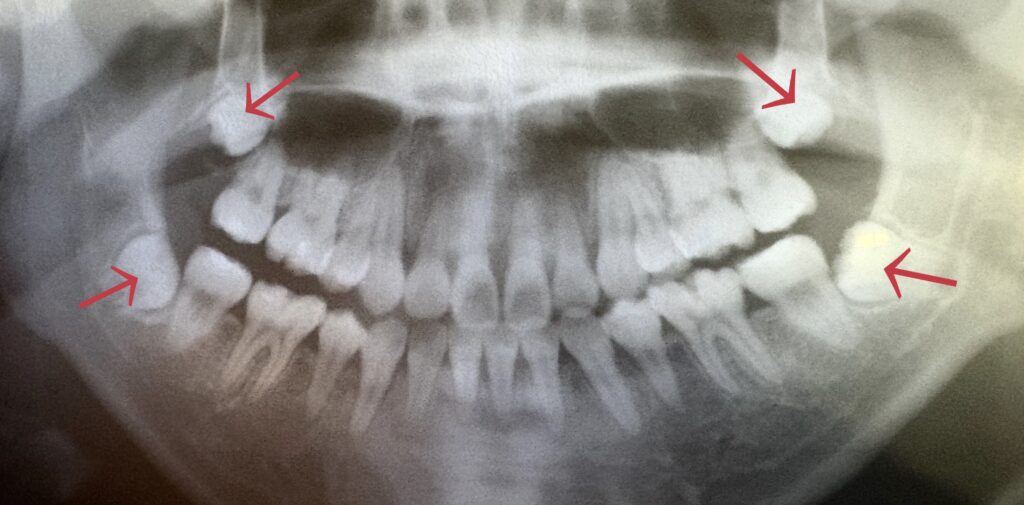

親知らずは「第三大臼歯(智歯)」といって、だいたい17〜25歳で奥に生えてくる一番奥の歯です。

生えてくる方向には特徴があります↓↓↓

下の親知らず → 前向きに生えることが多い

上の親知らず → 外向き(横向き)に生えることが多

生え方によって、隣の歯や矯正治療に影響を与えることがあります。